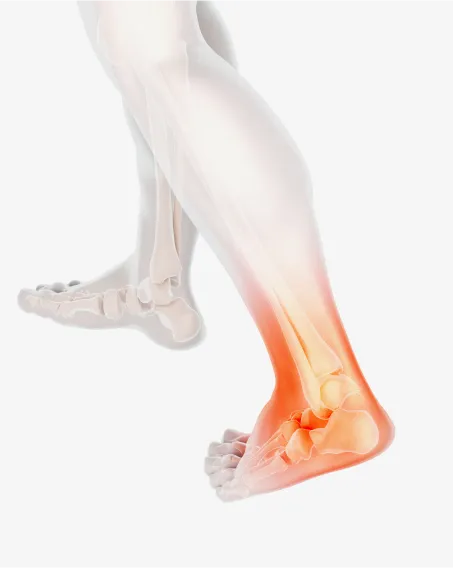

발목염좌

습관성 발목염좌는 일상생활이나 운동을 할 때 발목을 자주 접질리는 증상입니다.

발목관절을 지지하고 있는 인대에 비정상적인 외부 힘이 가해져 손상되거나 과하게 긴장되어 심한 경우에는 인대가 끊어진 상태를 말합니다.

발목터널증후군

발목 안쪽 복사뼈와 발뒤꿈치를 잇는 굽힘근지지띠의 안쪽 공간을 발목터널이라고 합니다.

이 부위가 다양한 원인에 의해 좁아지게 되면, 신경을 압박하게 되는데 이때 감각이 둔해지거나 전기가 통하는 듯 느끼는 증상입니다.